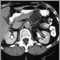

CT of the abdomenDefinition Return to top

An abdominal CT scan is an imaging method that uses x-rays to create cross-sectional pictures of the belly area. CT stands for computed tomography.